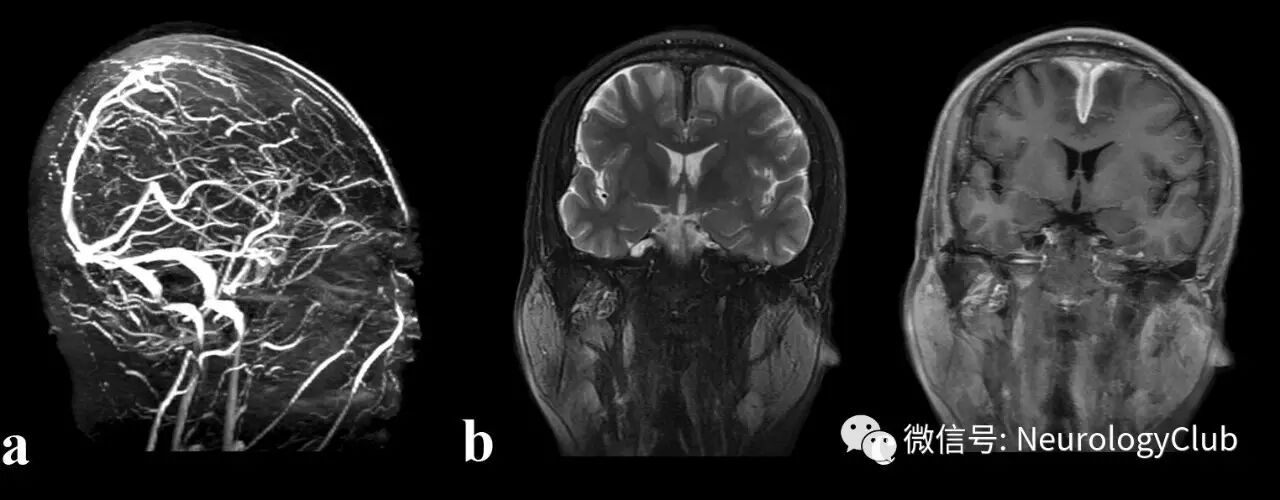

图2:特发性肥厚性硬脑膜炎患者;a:MRV可见上矢状窦闭塞;b:T2WI可见双侧额叶静脉性梗死;c:T1增强可见硬脑膜增厚强化